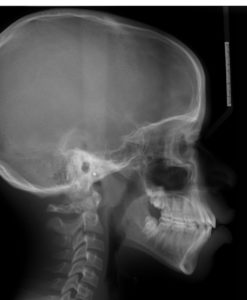

A 13.4-year-old African American male presents with a chief complaint that “My teeth look big.”